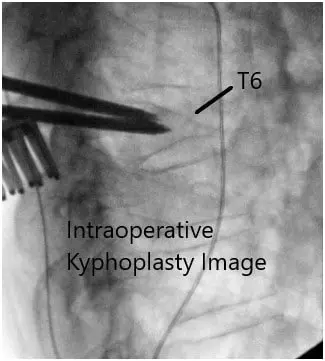

Intraoperative fluoroscopy images.

We employed fluoroscopy once again to check our level of operation and extended our incision slightly in the cephalad direction. At this point, we confirmed the level of the T6 vertebral body and started our open kyphoplasty.

First we inserted the Jamshidi needles under fluoroscopy through the pedicles to the vertebral body. We then inserted the cannulas for the kyphoplasty system bilaterally and obtained transpedicular biopsies, which were sent for histopathology.

At this point, we inserted the balloon on the patient’s right side and inflated it with contrast up to approximately 380 mmHg and this was checked constantly under both AP and lateral fluoroscopy simultaneously. We inflated the balloon to approximately 2 mL maintaining the pressure and to ensure that we remained within the confines of the vertebral body with the balloon inflation.